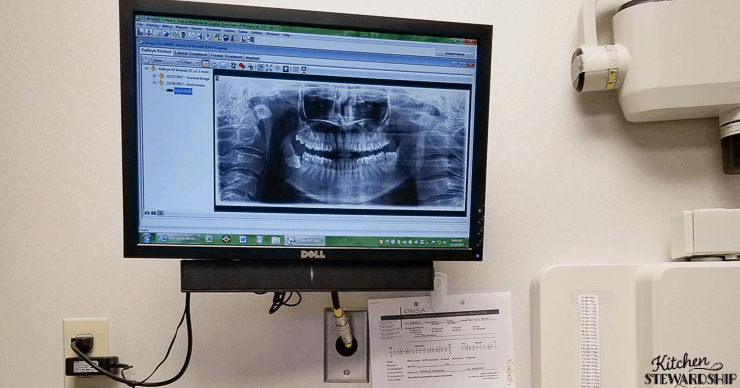

Two were fully “erupted” (they came in after I had my first child in my mid-20s!), one was halfway grown in, and one was completely “impacted,” i.e. under the surface of the gum.

A dentist or surgeon can look at an X-ray and determine if the root is wrapped around the bone or another tooth, or if the wisdom tooth itself is resting on the bone or an adjacent tooth. Those situations create greater risk.1, 2, 3, 4

Because it’s impacted, it’s going to be the hardest to get to. The doc has to break bone to extract it, and it’s also really close to the nerve. Nerve damage is one of the biggest risks to having your wisdom teeth out, at least in conventional risk lists.

- Get the whole tooth out. Risk = if the roots are close to the nerve, I could have temporary or permanent nerve damage. On the X-ray, it looks very close, but because X-rays are 2-D, it could be forward or backward from the root on a plane and really not a risky issue.

I am reading this as I sit here with my peas in hand on my jaw, after having a deeply impacted wisdom tooth removed after it developed a cyst and got an infection. Thankfully I have a wonderful oral surgeon, when I went in for my evaluation his recommendation was to only remove the one that had an infection and to leave the other two, because they posed no risk. The X-ray showed the roots over the nerve and he explained to me the risk of temporary or permanent nerve damage, which is why he recommended against removing the other lower wisdom tooth. Knowing I was concerned about my heart condition, he asked if I preferred local or general and said he would support me either way and when I opted for the local he told me it could be difficult because of the tooth position but that he would talk me through it.